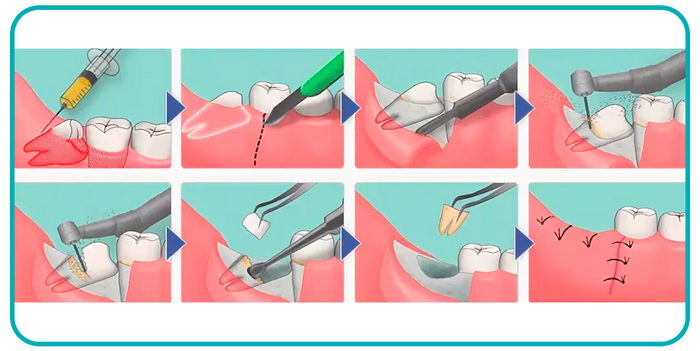

После того, как мы сделали анестезию, мы по необходимости производим разрез и отслаиваем слизистую оболочку с надкостницей от кости (слизисто-надкостничный лоскут) и бормашиной с водяным охлаждением выпиливаем костную стенку. Почему по необходимости? Потому что эти этапы зависят от степени прорезанности и расположения зуба. Чем более прорезан зуб, тем меньше разрез и меньше убираем кости. Иногда обходимся одним разрезом, иногда даже разрез не приходится делать, а просто распиливаем зуб. Короче, смотрим по ситуации.

По необходимости распиливаем сам зуб. Опять по необходимости? Конечно! Ведь надо смотреть по ситуации и соблюдать баланс между травматичностью и скоростью проведения операции. Если зуб лежит только под слизистой, корни сросшиеся и его можно достать элеватором, то не надо лишний раз его пилить. Достали, зашили и отпустили домой. Если же у нас зуб лежит криво и достать него просто так не получается, то тогда уже пилим либо зуб, либо подпиливаем кость.

После того как все удалили, мы чистим лунку от опилок и осколков, убираем оболочку фолликула, если он имел место быть, моем антисептиком. Обязательно пальцем щупаем на предмет острых краев лунки, чтобы потом они не прорезались. Если торчат, то убираем.

После обработки лунки мы кладем в неё либо гемостатическую губку, либо тромбоцитарную массу.

Если мы резали и откидывали слизисто-надкостничный лоскут, то кладем его обратно, и фиксируем швами. После швов обязательно контролируем остановилась ли кровь. Поэтому если врач сказал, что шов последний, не надо резко вскакивать и убегать.